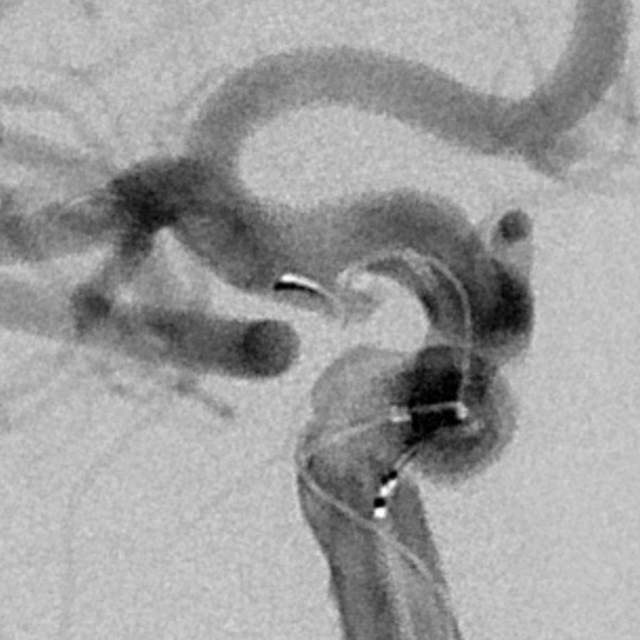

术中评估:动脉瘤位于后交通段的位置,靠近颈内动脉分叉部,颈内动脉交通段的长度相对短小,而且呈现喇叭口的形态,支架不容易锚定,容易出现跳跃“”嗑瓜子”现象。如果支架超过分叉部,覆盖大脑前动脉的起始部,可能会造成后续的大脑前动脉的血管变细。

手术难点:支架远端超过分叉部,操作简单;支架远端若紧邻分叉部近段,操做要求高。

手术过程:术中采用“一个支架+一个弹簧圈”的简约模式顺利结束手术,消除了动脉瘤破裂出血的风险。

手术结果:本次手术具有“创伤小、花费少、时间短、出院快”的特点,而且支架紧邻分叉部近段,没有覆盖大脑前动脉、支架打开贴壁良好、所有分支保持通畅~~~